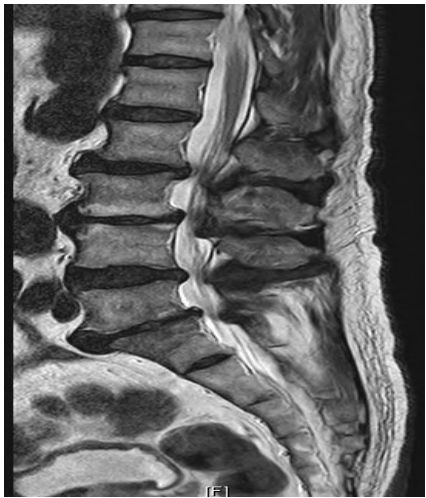

29. 74歲男性患者,主訴106年1月跌倒後無法久走久站,久走後右小腿痠痛,麻痺感已1年,大便秘,腹部 仍略脹氣,大便2天1行,服軟便劑,小便頻較困難,懷疑攝護腺腫大,夜尿3~4次,106年12月左大腿 外側麻痺感,小便頻,食慾稍增,經常口乾口破,核磁共振影像(MRI)如下圖,下列診斷何者最適當? (A)腰椎薦椎化 (B)梨狀肌症候群 (C)腰部扭傷 (D)腰椎退化性關節炎